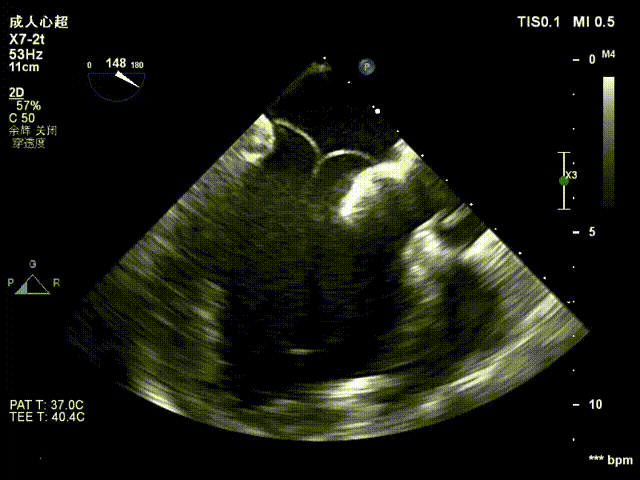

术前食道超声模拟

手术采用左侧第六肋间微创5cm切口心尖入路,在超声引导下,清晰识别MitraFix®输送系统准确跨瓣,并将人工瓣膜准确释放于二尖瓣瓣环,瓣膜释放后支架贴合牢固,术后无反流,二尖瓣前向血流通畅、跨瓣压差1mmHg,左心室流出道通畅,流出道血流速度为1 m/s. 后顺利撤出输送系统,关闭心尖切口,手术顺利结束。

术后瓣叶工作情况

术后无反流